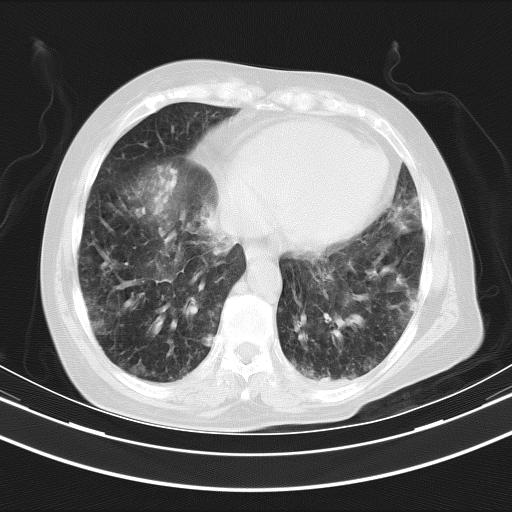

双肺多发淡片影,毛玻璃影,,支持支气管肺炎,,建议血气找原因,,嗜睡是否肺性脑病?有没有慢支病史?

1)两肺感染性病变;建议抗炎治疗后复查。2)纵隔淋巴结肿大。3)左侧胸腔积液。

1)先考虑两肺感染性病变;建议抗炎治疗后复查。

2)纵隔淋巴结肿大。

3)左侧胸腔积液。